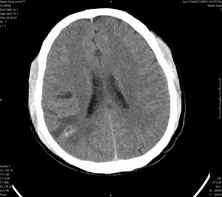

男,41岁,间断抽搐1小时,失神5分钟,bp130/90mmhg。低密度区ct值约16hu。

脑实质见多发散在的钙化点,左顶叶见一囊变灶,多考虑脑囊虫。

脑囊虫,部分囊内见头节。

脑实质见多发散在的钙化点,右颞、顶叶见囊性灶,考虑脑囊虫。

多发的囊泡(多发囊型)+多发的钙化(慢性钙化型)=混合型

顶叶最大的囊直径2.2cm,如果考虑囊虫的话,囊是不是有点儿太大了?